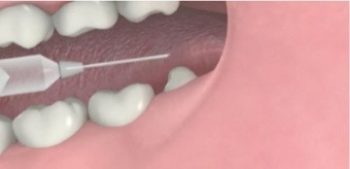

2. ฉีดยาชา เพื่อลดอาการเจ็บปวดขณะผ่า